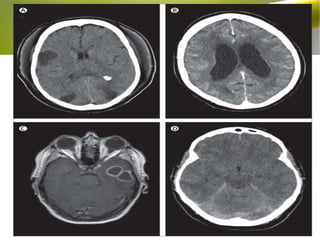

RADIALOGICAL DIAGNOSIS:

• Cranial computed tomography (CT) is of limited use in acute

BM. CT in cerebral oedema may show slit-like lateral ventricle

and areas of low attenuation.

• Diffuse meningial enhancement may be seen.

• The main indications for a CT scan in meningitis when it is

preferred as a first line investigation prior to LP are:

a. Signs of ↑ICT (e.g. papilloedema)

b. Suspecting malignancy( focal neurological deficits).

c. Deteriorating neurological status.

d. Previous neurosurgical procedure or trauma.

e. Immunocompromised.

• Normal CT scan does not exclude the risk of raised ICT.